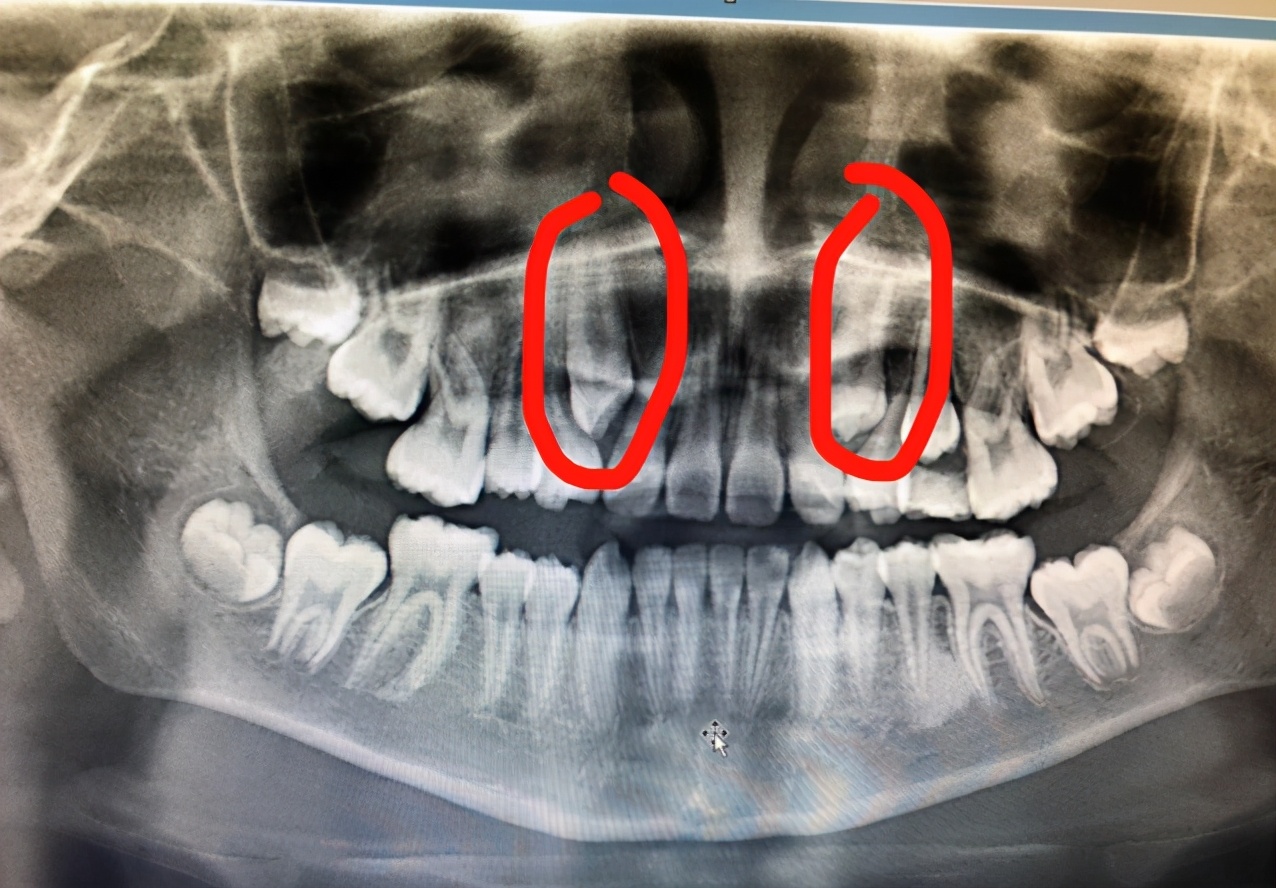

这就要从它的“身世”说起了:一般儿童在6~7岁左右开始换牙,但是尖牙换牙时间往往比其他牙齿晚,如果乳尖牙因龋齿或外伤过早脱落,恒尖牙又没那么快长出来,那么尖牙的位置就会被早萌出的邻恒牙霸占。等恒尖牙长出来时,就只能委委屈屈地被挤到牙列外面,看着像老虎的獠牙,故被称为*牙虎**。

孩子14岁前后,颌骨还在生长发育,随着颌骨的长大,在牙列的自行调整过程中,*牙虎**还有“归队”的可能。如果到了17岁*牙虎**还在原位不动,那时可去找口腔科医生诊治,将*牙虎**后面的那颗牙拔掉,在唇颊肌肉的协同压力作用下,有可能把*牙虎**“请回”到正常牙列中去。